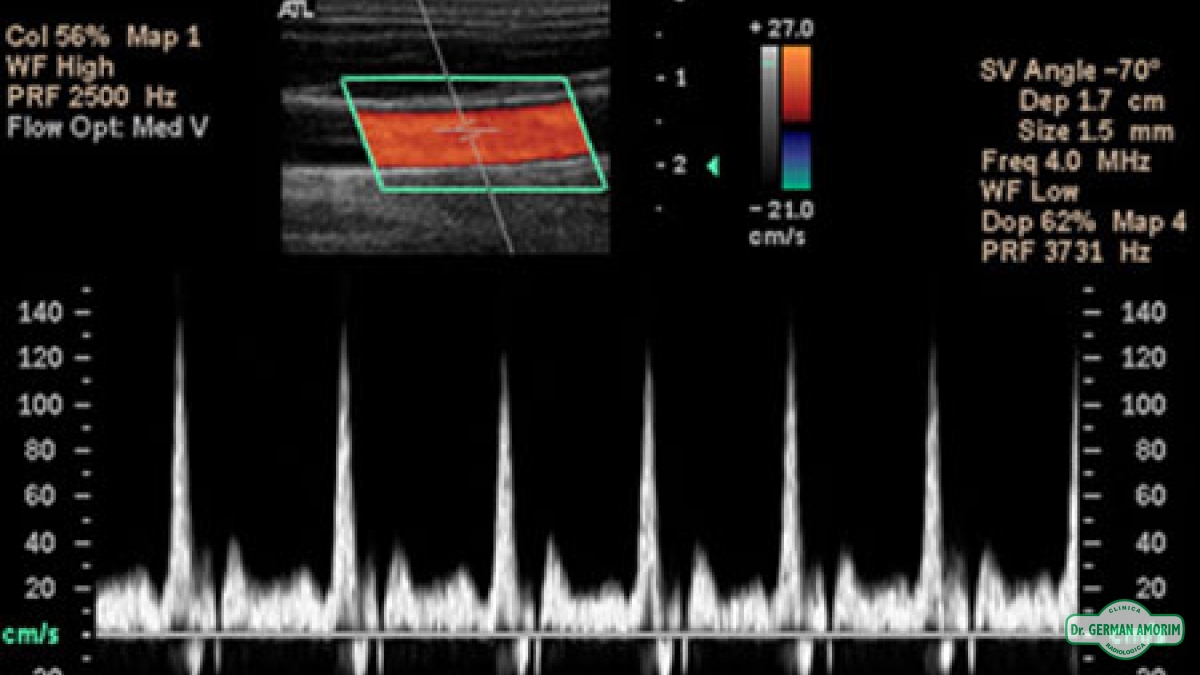

La ecografía-doppler es un tipo de ecografía con la que se estudia el flujo de sangre que pasa a través de las arterias y venas, y que permite conocer su cantidad y velocidad en un momento concreto.

Se convierte en una técnica obligada y especialmente útil cuando se sospechan enfermedades trombóticas de arterias o venas. También se utiliza de forma rutinaria en las ecografías durante el embarazo estudio tiroideo.

Para realizar estos estudios es necesario y equipo y trasductores especiales.